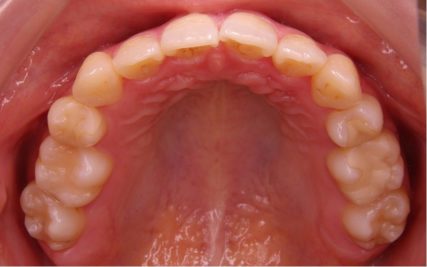

でこぼこ/20代女性

- 不正咬合/叢生(でこぼこ)

- 上下とも前歯のスペース不足が認められた。歯のサイズと顎の幅とのバランスが不調和な事が原因の1つとして考えられる。

- 上顎両側4番・上顎両側8番・下顎両側4番・下顎両側8番抜歯

- 前歯部のでこぼこが解消され、正常咬合を獲得する事が出来た。又、歯科矯正用アンカースクリューを用いる事で抜歯スペースを有効に利用できた。